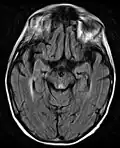

Frequently, secondary to thiamine deficiency and subsequent cytotoxic edema in Wernicke encephalopathy, patients will have marked degeneration of the mammillary bodies. Thiamine (vitamin B1) is an essential coenzyme in carbohydrate metabolism and is also a regulator of osmotic gradient. Its deficiency may cause swelling of the intracellular space and local disruption of the blood-brain barrier. Brain tissue is very sensitive to changes in electrolytes and pressure and edema can be cytotoxic. In Wernicke this occurs specifically in the mammillary bodies, medial thalami, tectal plate, and periaqueductal areas. People with the condition may also exhibit a dislike for sunlight and so may wish to stay indoors with the lights off. The mechanism of this degeneration is unknown, but it supports the current neurological theory that the mammillary bodies play a role in various "memory circuits" within the brain. An example of a memory circuit is the Papez circuit.